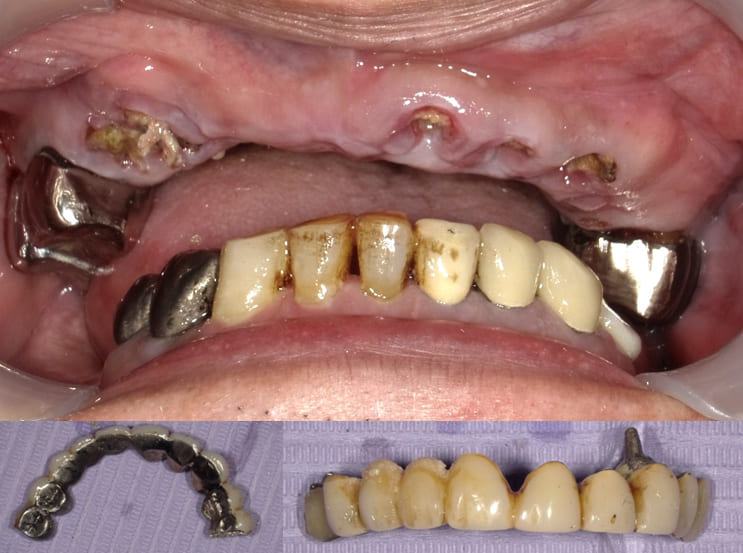

Case.01(40歳代 女性)

臼歯の Vertical stop の獲得と前歯の咬合・審美の改善のための治療を行った症例

歯科恐怖症で歯科医院に受診できずに奥歯がどんどん崩壊して噛むことができず前歯も割れたので全顎的な治療を希望して来院。

全顎的インプラント治療が必要となるケース。

初診時のパノラマX-P所見

#17,15,14,13,23,24,27,36,44,45,46,47 が残根状態で温存は不可能であり、患者さん自身もそれを自覚しておられた。